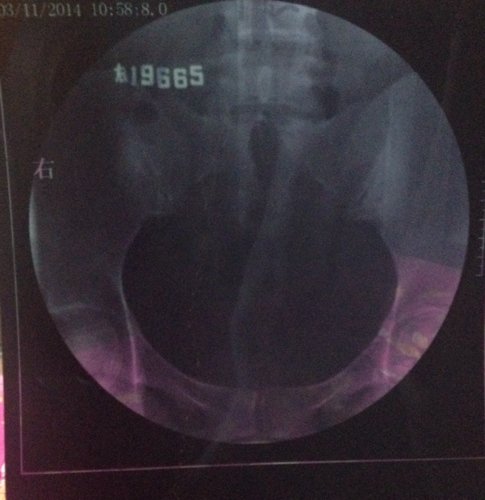

上个月输卵管造影的结果,这个月想试孕又发现卵泡没排出来,现在纠结要不要打促排卵针,片子上看起来严重 上个月输卵管造影的结果,这个月想试孕又发现卵泡没排出来,现在纠结要不要打促排卵针,片子上看起来严重吗?这个月是右卵巢有优势卵泡。医生帮忙看下,我这情况能打促排卵针吗? 点击展开 匿名用户 2014-05-11 00:08 为您推荐: 其他回答 病情分析: 你好,应该予以手术治疗的 指导意见: 可以考虑腹腔镜手术来治疗,术后注意不可过早恢复同房,及时复查。 独水凡_xjeq 2014-05-11 10:34 相关问题 3月做的输卵管造影,两侧通而欠畅,4月做卵泡监测,发现卵泡大了不排,5月刚打了促排卵针,请问我宫外 之前做造影,结果是左侧通,右侧不通,后来做输卵管通液通了,现在右侧卵泡2 1请 请问:(南京鼓楼医院)做(生殖激素测定+基础卵泡检查)跟(子宫输卵管浀造影)跟(甲功三项)大概